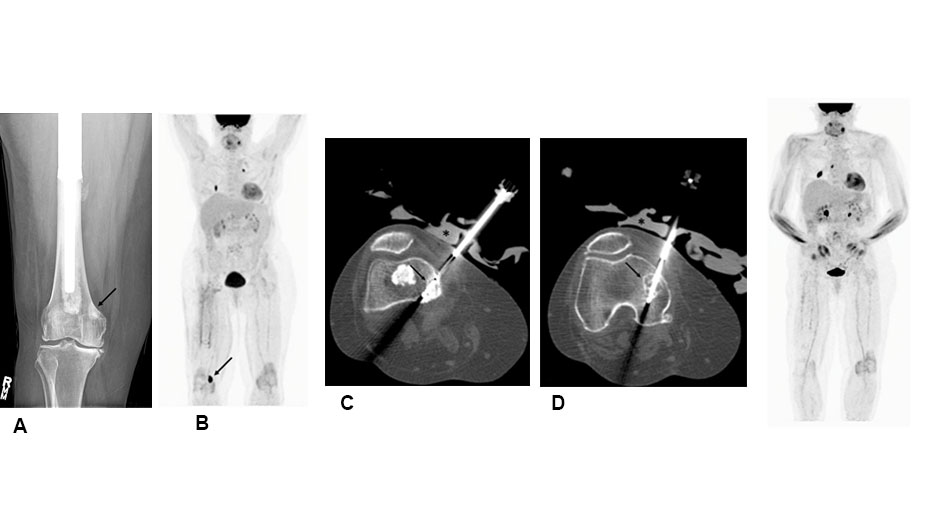

Cryoablation is a technique to relieve pain. It uses image guidance to place a cooling probe within a bone metastasis. In this case, it is a femur metastasis just above the knee joint (A & B). Once positioned (C & D), the probe is cooled so that the cancer is ablated through freezing.

Radiofrequency ablation (RFA) is a technique to relieve pain and restore function. When a deposit of tumor is identified by PET (A, arrow) or MRI (B, arrow), image guidance is used to place an RFA needle probe within it. In this case, the probe (C, arrow) ablates that tumor tissue through heat.